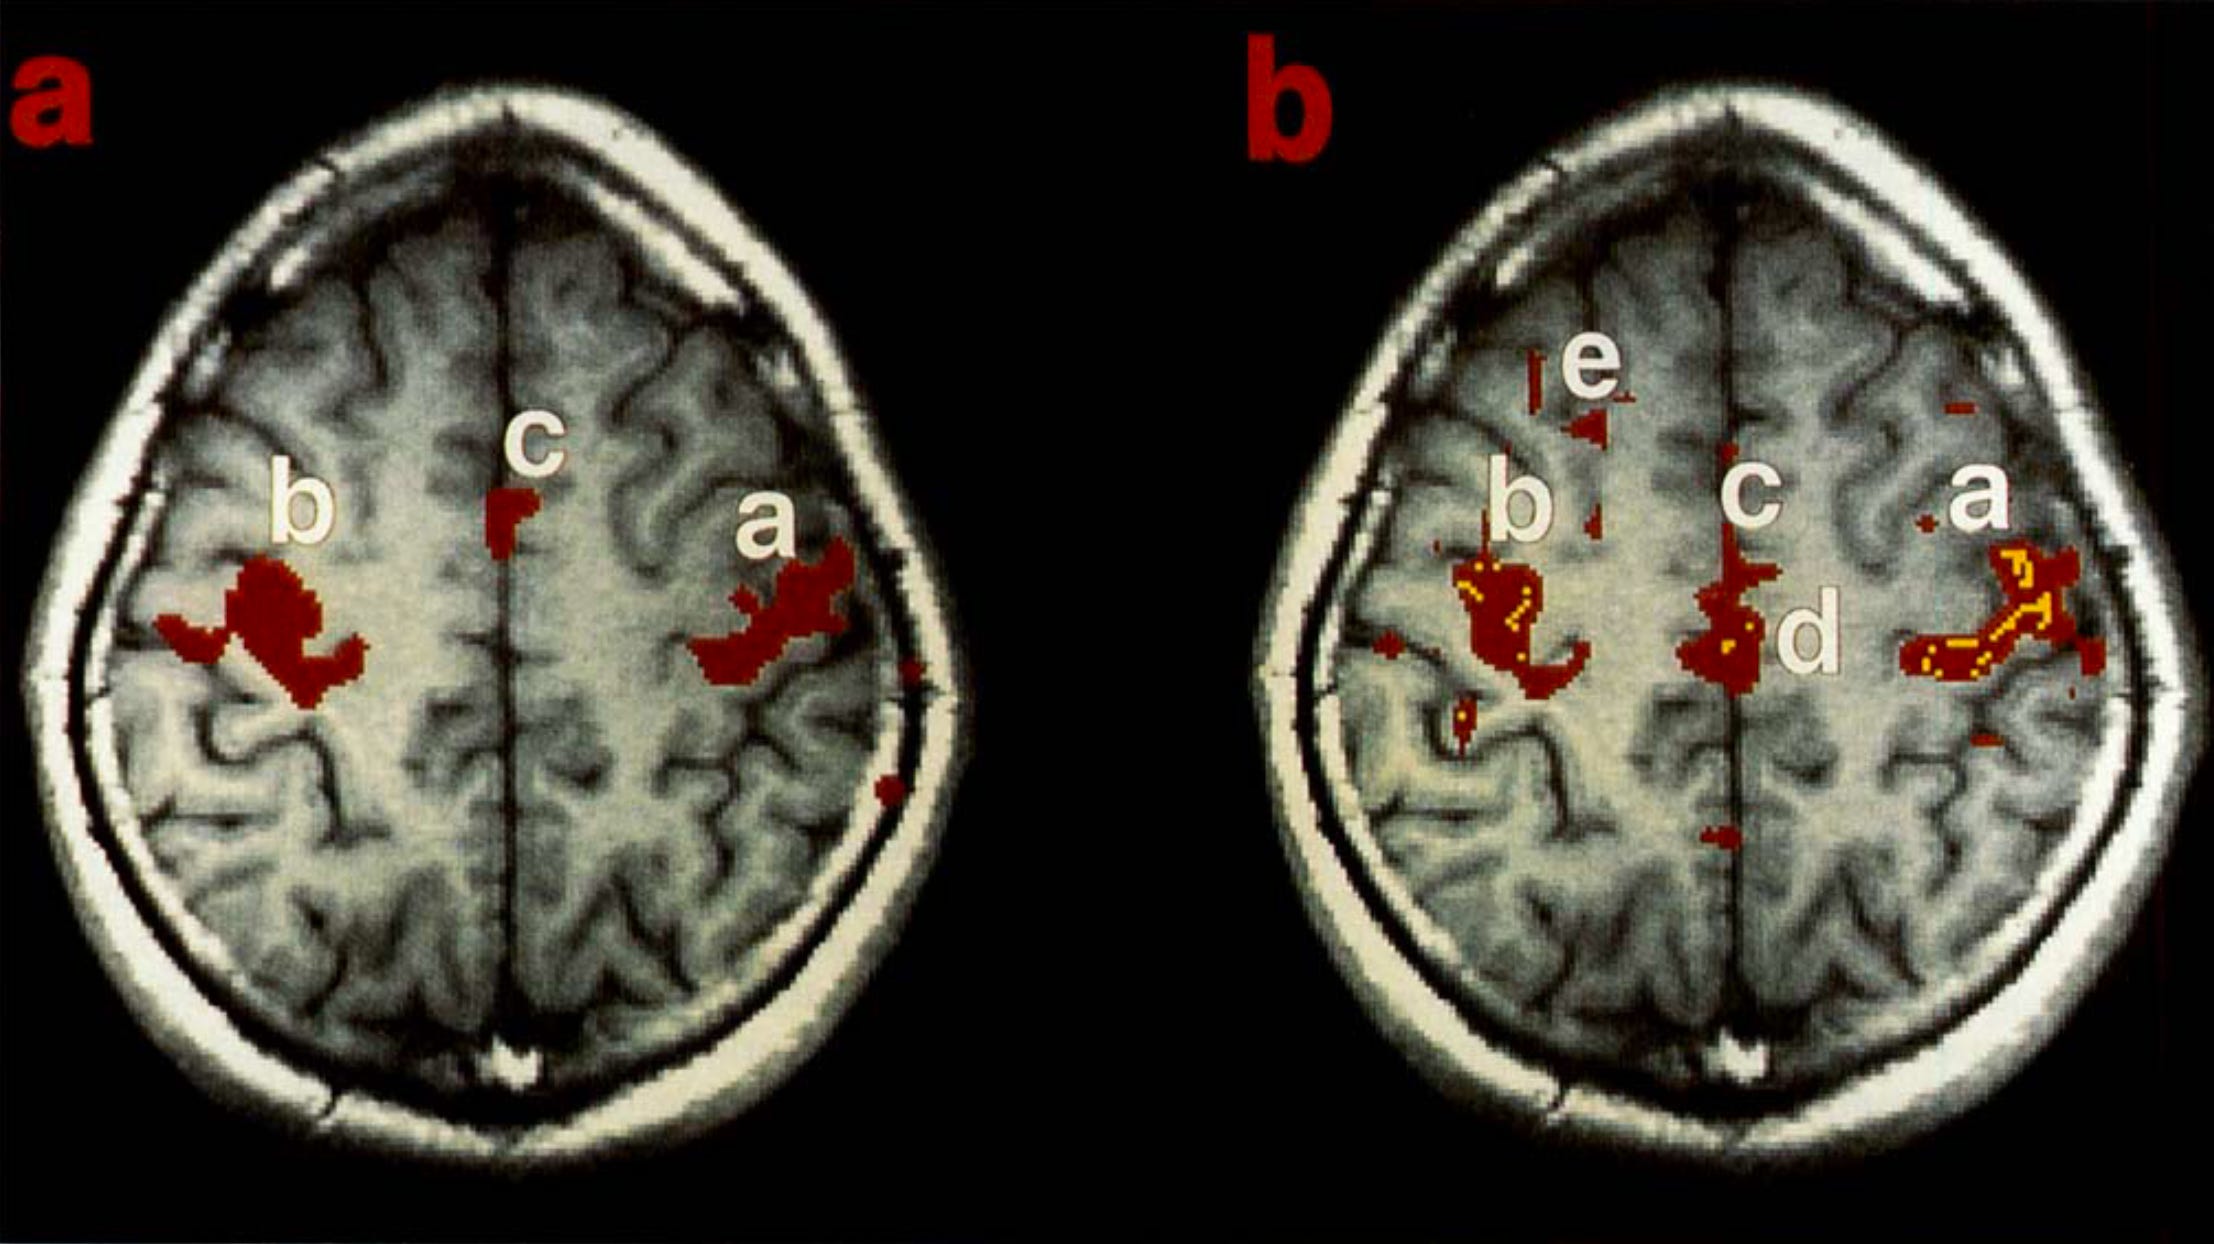

![Figure 1. [Biswal et al. (1995)] (a) Finger-tapping task activations for one subject. | (b) Functional connectivity analysis using a central “pixel” in blob “b” showing positive (red) and negative (yellow) correlations. Figure 1. [Biswal et al. (1995)] (a) Finger-tapping task activations for one subject. | (b) Functional connectivity analysis using a central “pixel” in blob “b” showing positive (red) and negative (yellow) correlations.](https://substackcdn.com/image/fetch/$s_!xTP8!,w_1456,c_limit,f_auto,q_auto:good,fl_progressive:steep/https%3A%2F%2Fsubstack-post-media.s3.amazonaws.com%2Fpublic%2Fimages%2F20db3cb6-442e-4325-a99f-93ec3cbf5ed5_2214x1244.png)

Biswal et al. (1995) is the study that set the field in motion, laying the groundwork for the discovery of whole-brain functional networks, including the DMN. Researchers wanted to know if there is an underlying organization to spontaneous low-frequencey fluctuations (<0.1 Hz) observable in the resting human brain via functional MRI (fMRI). They scanned eleven healthy individuals while they performed a bilateral finger-tapping task to identify regions of the sensorimotor cortex. Resting-state time-series were additionally acquired and used to compute correlation coefficients within these areas. Authors reported a “high degree of temporal correlation” within and across hemispheres in regions of the brain associated with motor function (Figure 1). This paper introduced the paradigm of functional connectivity, demonstrating that naturally-occurring resting-state brain fluctuations are structured and coherent, while paving the way for future studies to uncover the organization of the DMN using the same method.